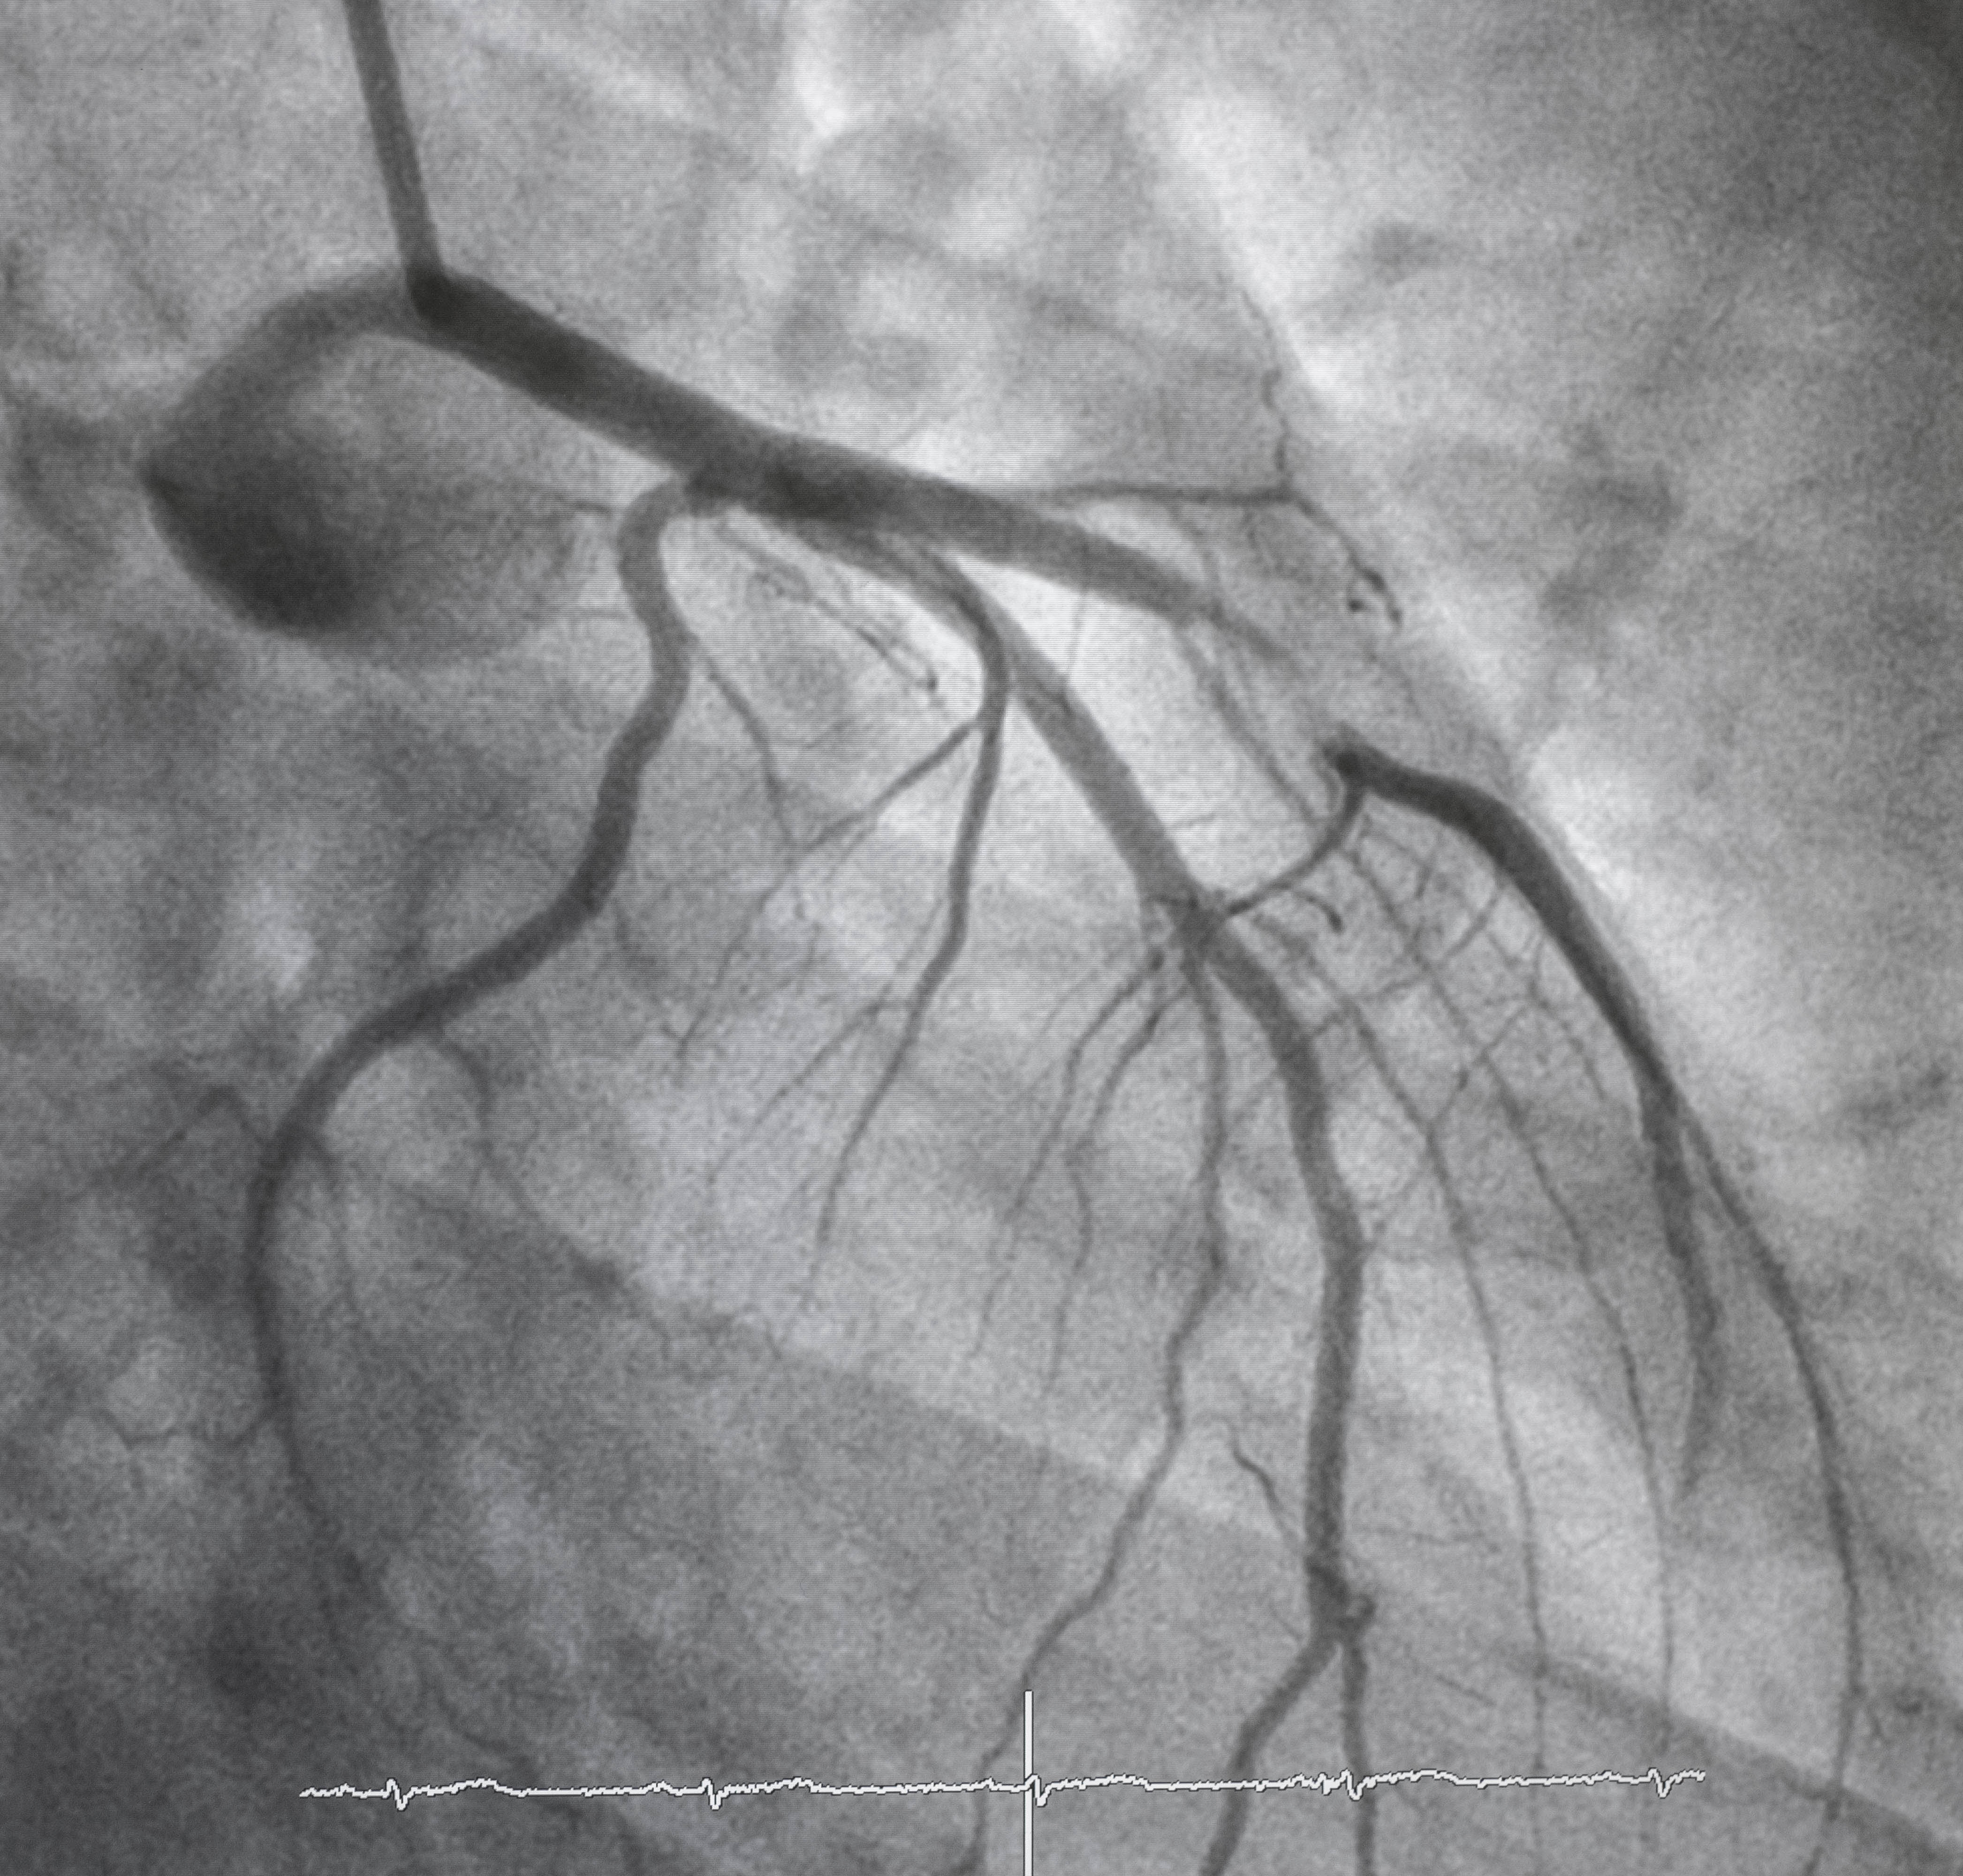

Continuous Learning Through Peer Review Makes Angioplasty and Stenting Better in Michigan